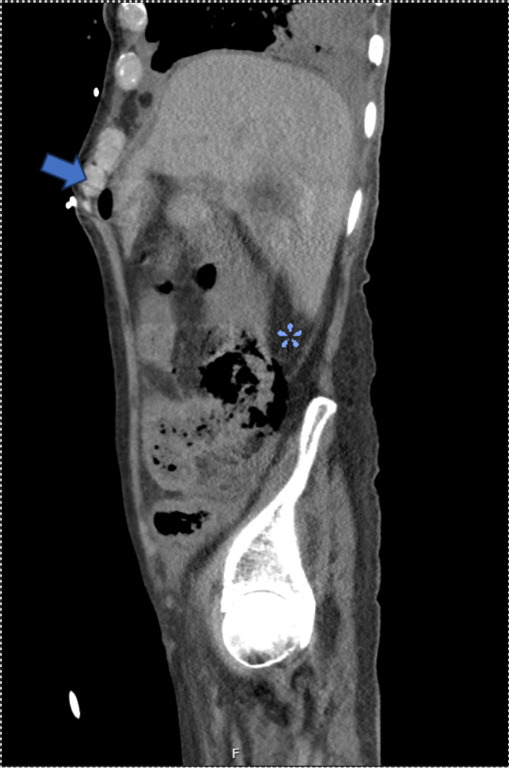

Case description: We present herein the first reported case of peritonitis secondary to jejunal and cecal perforation secondary to angio-IA after lung transplantation (LT) in a 62-year-old male. The patient was admitted to the hospital for acute cellular rejection requiring high-dose immunosuppression. His course was complicated by respiratory failure secondary to IA, with resulting multiorgan system dysfunction during which time peritonitis was noted on examination and cross-sectional imaging demonstrated pneumatosis, portal venous gas, and pneumoperitoneum. The patient required emergent surgical intervention and underwent an exploratory laparotomy, jejunal resection, right hemicolectomy, and end ileostomy with colonic mucus fistula. Final pathologic analysis of resected specimens demonstrated angio-IA in both the jejunal and cecal segments with associated transmural ischemic necrosis.